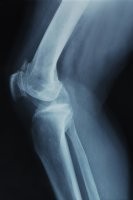

Megnöveli a reumatoid artritisz gyakoriságát az elhízás terjedése: egy új tanulmány szerint a jelentős testsúlygyarapodás a fájdalmas, krónikus betegség, a reumatoid artritisz (RA) kockázatát is növelheti, különösen elhízott nők esetében.

Az Arthritis Care & Research szaklapban megjelent, 1985 és 2007 között végzett kutatás eredményei ráadásul azt mutatták, hogy az elhízás megelőzi az RA megjelenését. Az elhízás RA-ra gyakorolt hatása a kutatásban jelentősebbnek mutatkozott a nők esetében, ami valószínűleg azzal magyarázható, hogy a nőkben amúgy is háromszor gyakrabban jelentkezik a betegség, mint a férfiakban.

Az RA az Egyesült Államok lakosságának körülbelül 1 százalékát érinti. Az autoimmun betegség az ízületi szöveteket, és néha a szerveket is támadja, gyulladást, duzzanatot, lázat és kimerültséget okozva. A betegség bármikor jelentkezhet, de leggyakrabban 30 és 60 év között alakul ki. A betegséget genetikai és környezeti tényezők is befolyásolják.